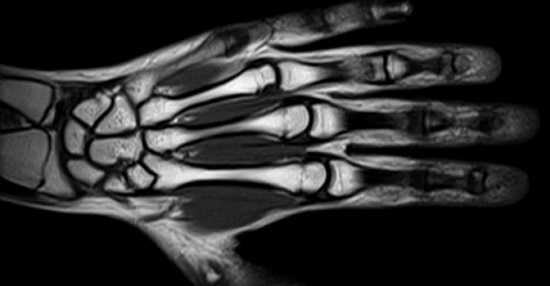

Магнитно-резонансная томография кисти и лучезапястного сустава

При подозрении на развитие онкологического процесса назначают контрастное МР-сканирование. Ткани опухоли способны накапливать хелаты гадолиния, что позволяет визуализировать очаги размером от 3 мм. Кровеносная сеть новообразований имеет характерные особенности. Злокачественные опухоли отличаются извитостью сосудов и большим количеством анастомозов. При использовании контраста врач может предположить малигнизацию процесса на основании рисунка кровеносной системы. Окончательный диагноз ставят по результатам биопсии.